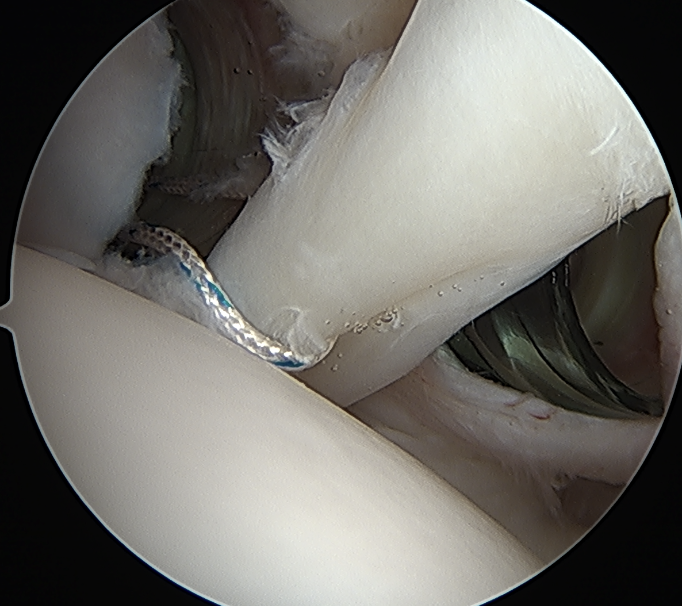

Arthroscopic suprapectoral biceps tenodesis

Technique

- tag biceps tendon with high strength suture and release

- repair superior labrum with one or two anchors

- anchor biceps tendon into bicipital groove

Portal just anterior to supraspinatus tendon

Tag biceps and release

Anchor biceps tendon into bicipital groove